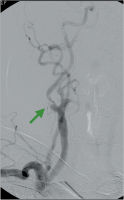

Subtraktionsangiographie

Abbildung 10: Subtraktionsangiographie. Hochgradige Abgangsstenose der rechten Art. vertebralis.

Abbildung 11: Subtraktionsangiographie. Hochgradige, exzentrische Abgangsstenose der rechten Art. carotis interna (grüner Pfeil).